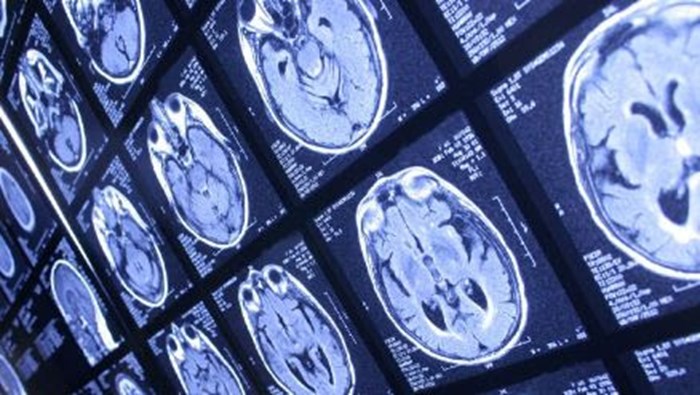

سبک زندگی- رمزگشانیوز؛ ایسنا به نقل از شینهوا نوشت: این مطالعه که در مجله Nature Medicine منتشر شده است، ۲۹۴ بزرگسال ۵۰ تا ۹۰ ساله با عملکرد طبیعی مغز را تا ۱۴ سال پیگیری کرده و تعداد گامهای روزانه، عملکرد مغز و تجمع پروتئینهای مرتبط با آلزایمر نظیر «تائو» در مغز آنها را زیر نظر داشته است.

در این مطالعه آمده است که افزایش فعالیت بدنی با کاهش سرعت زوال عملکرد مغز مرتبط است که به نوبه خود با تجمع کندتر پروتئینهای مرتبط با آلزایمر در مغز ارتباط دارد.

طبق این مطالعه، شرکتکنندگانی که بیش از ۵۰۰۰ قدم در روز برمیداشتند، کاهش کندتری در حافظه و تفکر نشان دادند که با کاهش تجمع تائو، پروتئینی مرتبط با پیشرفت آلزایمر، مرتبط بود.

متخصصان گفتند که تجمع تائو و زوال شناختی در سطح فعالیت متوسط ۵۰۰۱ تا ۷۵۰۰ قدم در روز ثابت ماند و افزودند که حتی فعالیت متوسط، حدود ۳۰۰۰ تا ۵۰۰۰ قدم با کاهش قابل توجه تجمع تائو و زوال شناختی مرتبط است.